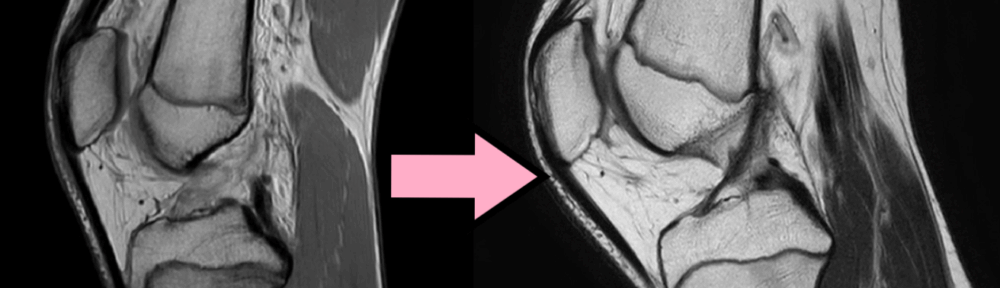

- 30 marzo 2023: RM n.1 = rottura completa del legamento crociato anteriore (LCA).

- Letture indipendenti (3 radiologi): concordi, classificazione di Ihara III (rottura con monconi dislocati).

- Data: 2 agosto 2023 (RM n.2)

- Letture indipendenti (3 radiologi): concordi, ACLOAS grado 2.

- Reperti: continuità ripristinata; non spessore pieno, ma spessore e tensione legamentosa definiti.

- RM n.1 (2023/03/30): Ihara III (concorde, 3/3 lettori).

- RM n.2 (2023/08/02): ACLOAS grado 2 (concorde, 3/3 lettori).